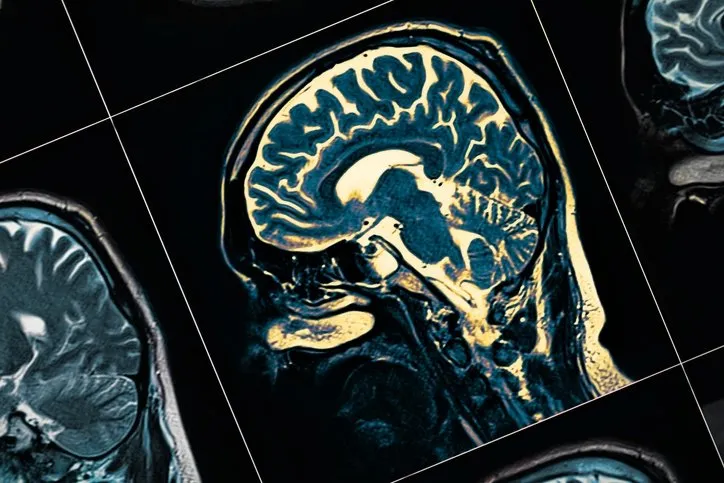

Alzheimer hastalığı, genellikle ilerleyen yaşla birlikte sinir hücrelerinin zamanla hasar görmesiyle ortaya çıkan bir hastalıktır. Bu rahatsızlık, genellikle hafıza kaybı, bilişsel bozukluklar ve kişilik değişiklikleri ile kendini gösterir.

Alzheimer hastalığının kesin nedeni tam olarak bilinmemekle birlikte, genetik faktörler, yaş, cinsiyet ve çevresel etkenlerin rol oynadığı düşünülmektedir. Maalesef, Alzheimer hastalığı henüz tamamen tedavi edilebilir bir durum değildir, ancak araştırmalar erken fark edildiği durumlarda gelişmesini engellenebileceğini ve hatta durdurulabileceğini gösteriyor.

Aging and Disease dergisinde yayınlanan araştırmada, Alzheimer hastalarında tipik olarak görülen herhangi bir iltihaplanma ve "plak ve düğümlere" odaklanarak, 40 ila 60 yaşları arasındaki "bilişsel açıdan sağlıklı" 54 katılımcının beyin MR'larını ve PET taramalarını analiz edildi.